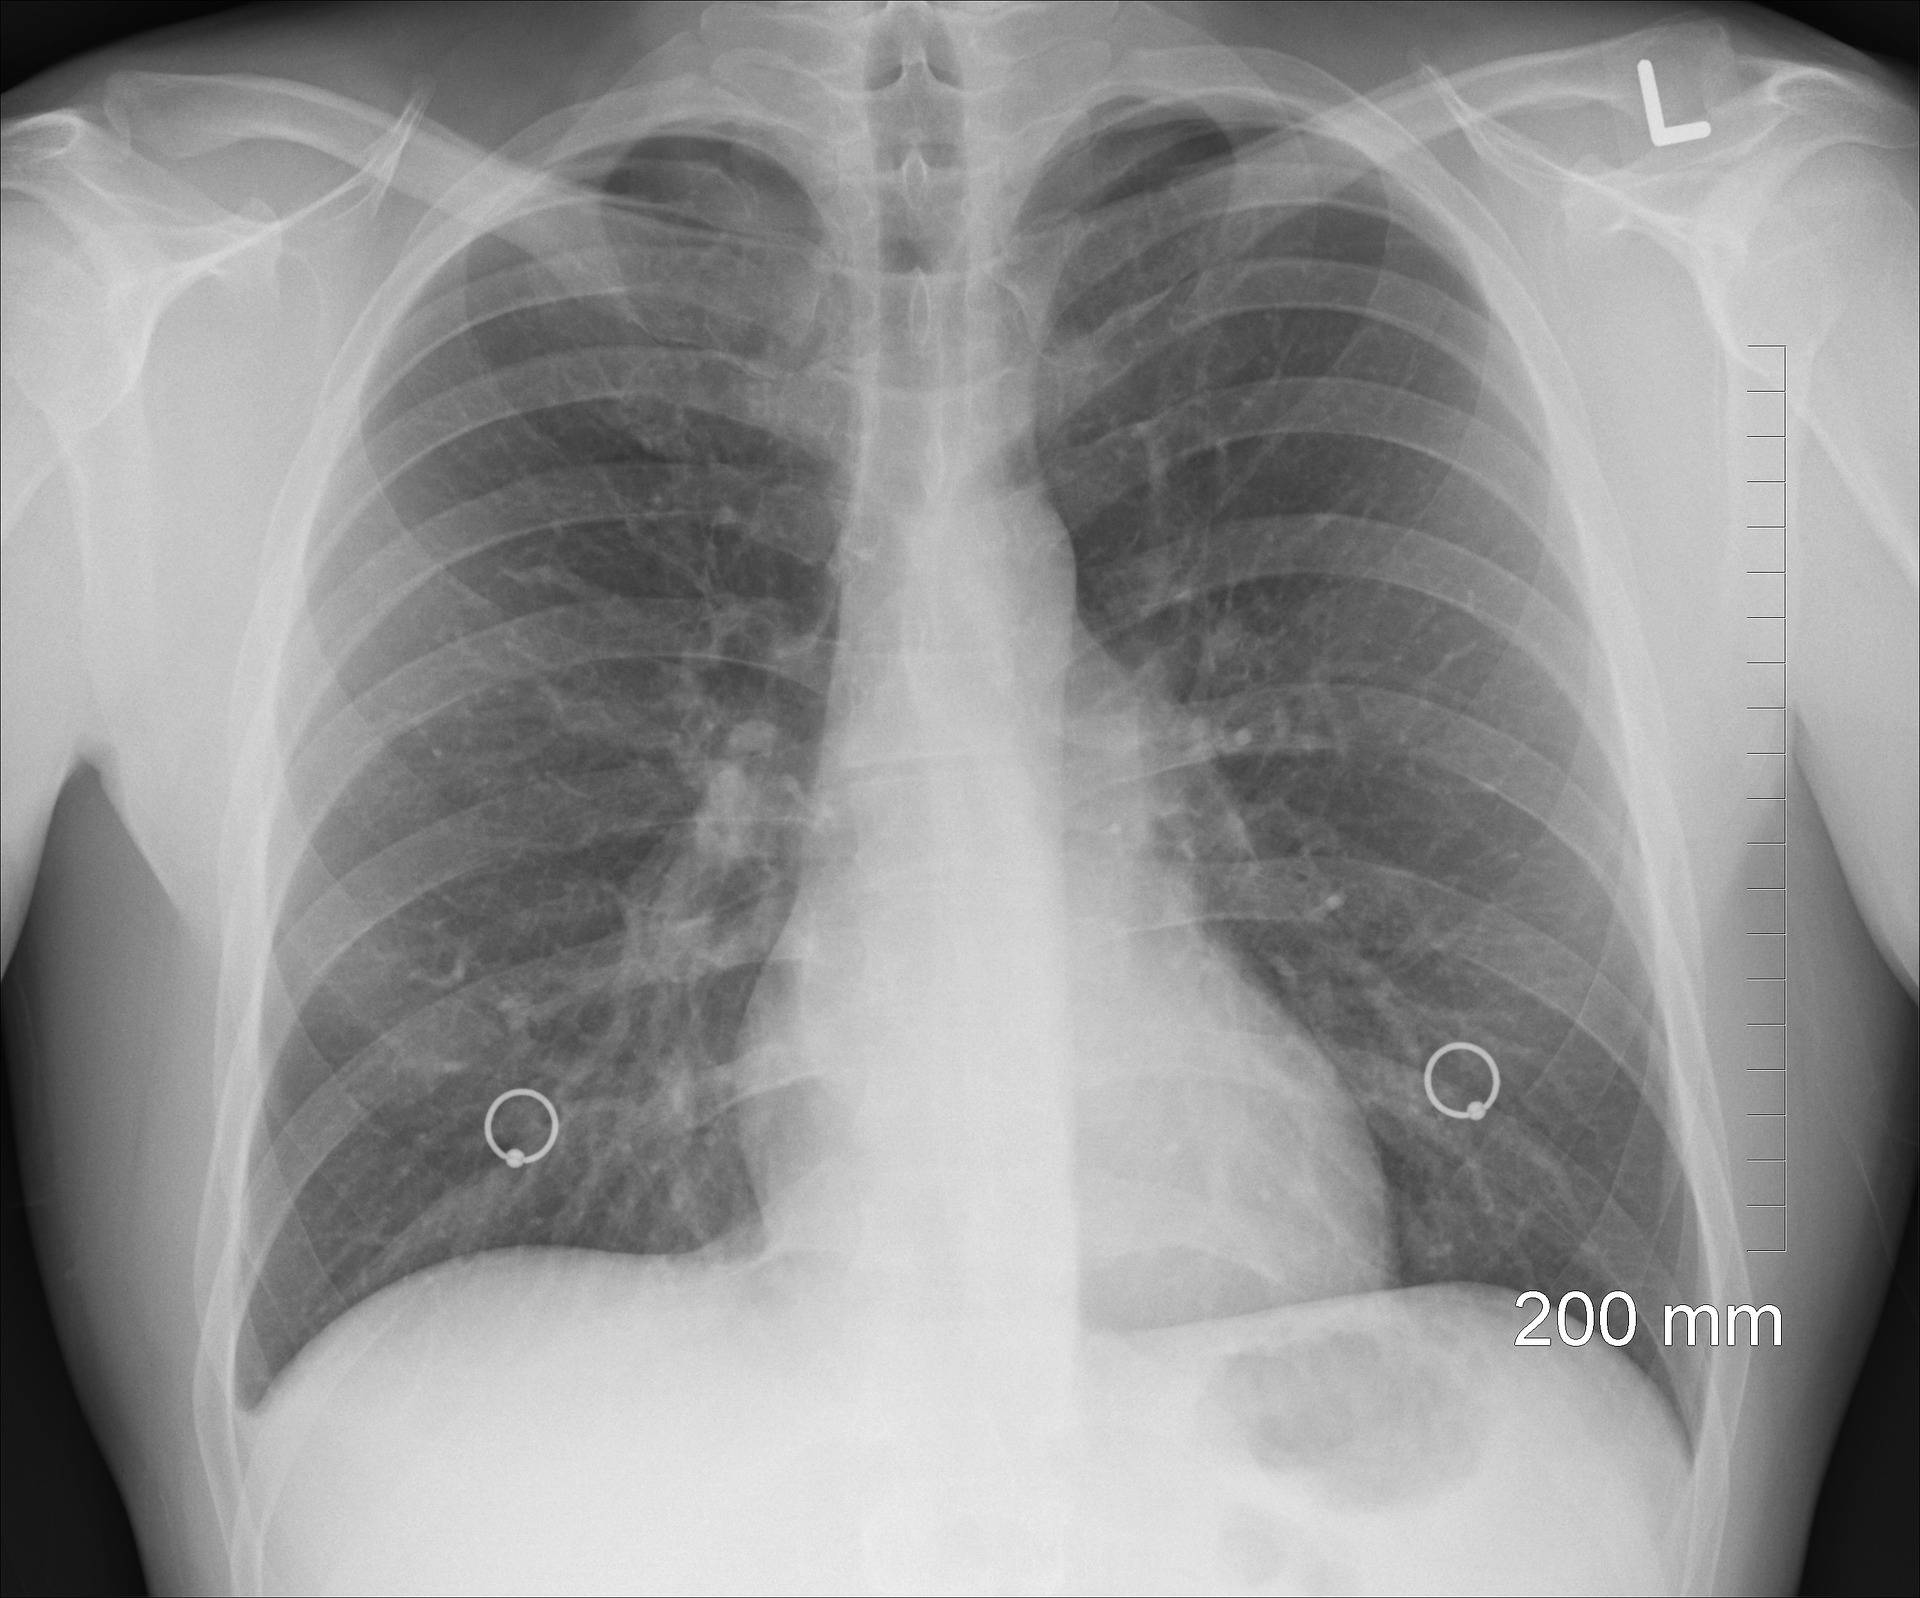

Uma equipe de cientistas da computação vinculada à Universidade Estadual de Maringá (UEM) conseguiu desenvolver um método para identificar casos de pneumonia causados pela Covid-19 a partir de imagens de raio-x. O estudo, feito a partir de uma base internacional de dados, teve um acerto de 90% dos casos, e a boa notícia é que utiliza um equipamento de custo baixo e disponível em praticamente toda a rede de saúde. Os pesquisadores pretendem agora ampliar a investigação, com parceria de profissionais da área médica.

A base de dados utilizada tem imagens de raio-x de pessoas sadias, de pessoas com pneumonia causadas por agentes variados e causada pelo novo coronavírus. Criando uma hierarquia de dados dos microorganismos relacionada às texturas observáveis no raio-x, a equipe conseguiu comprovar o diagnóstico em 90% dos casos. Apesar do raio-x não oferecer uma imagem tão detalhada quanto a de uma tomografia, por exemplo, o resultado é rápido e barato.